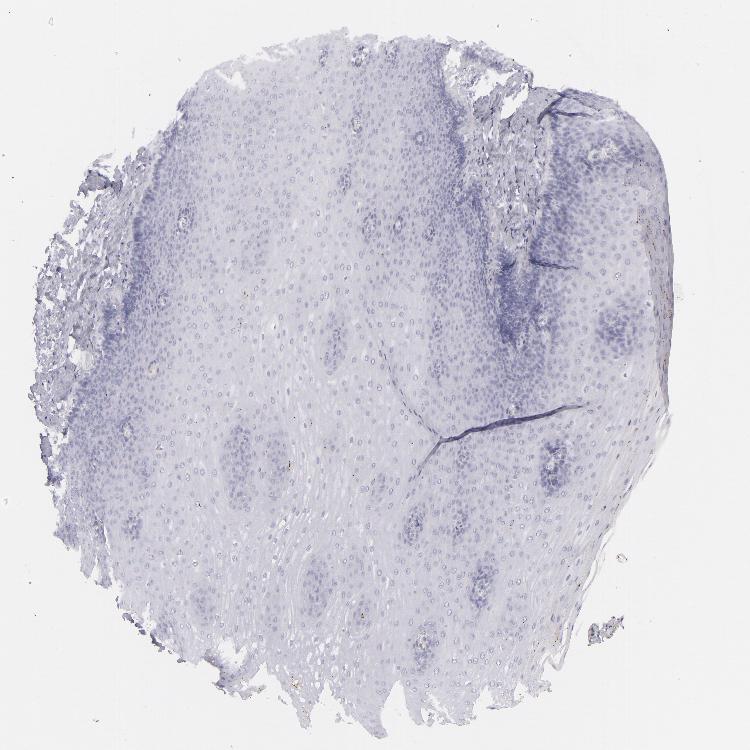

ESOPHAGUS - Antibody stainingi

Antibody staining in the annotated cell types in the current human tissue is reported as not detected, low, medium, or high, based on conventional immunohistochemistry profiling in selected tissues. This score is based on the combination of the staining intensity and fraction of stained cells.

Each image is clickable and will lead to virtual microscopy that enables deeper exploration of all samples and also displays staining intensity scores, fraction scores and subcellular localization as well as patient and tissue information for each sample.

Antibody HPA030188Antibody HPA030189Antibody CAB002210

Squamous epithelial cells MediumMediumNot detected